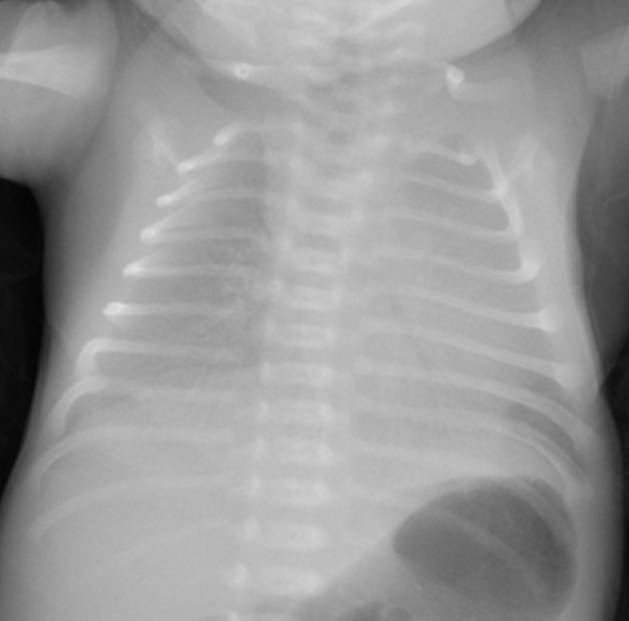

典型胸片結(jié)果:

(白肺表現(xiàn),IV級(jí)肺透明膜病變)

(II-III級(jí)肺透明膜病變)